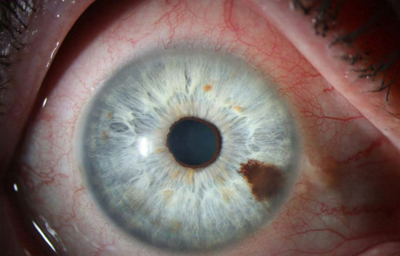

Nódulos de Lisch

Archivo Fotográfico Dr. Francisco Barraquer.

Nódulos de Lisch

Archivo Fotográfico Dr. Francisco Barraquer.

Hamartomas - Nódulos de Lisch. Son estructuras benignas, nodulares, de aspecto gelatinoso, implantadas con pedículo sésil sobre la superficie de la hoja anterior del Iris, compuestas por proliferación de células histológicamente maduras, de origen melanocítico normales del tejido en el que residen, de color que varía del castaño claro al castaño oscuro y generalmente de ± 1.0mm. Cuando se asocian a la Neurofibromatosis de Von Recklinghausen, se las considera patogneumónicas y se las denomina nódulos de Lisch (24, 25,26)